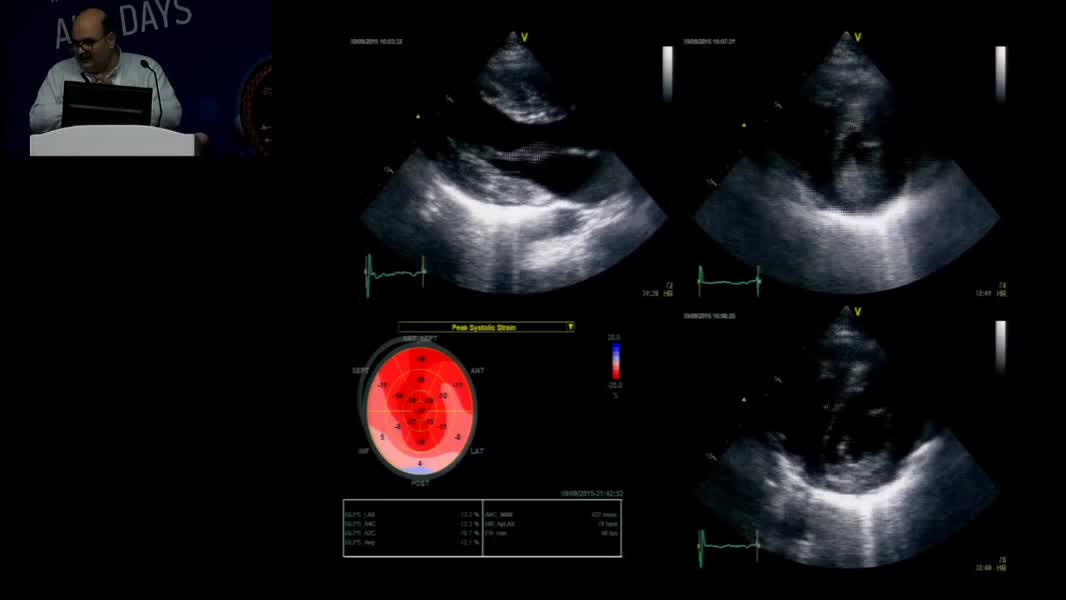

Echocardiographic Face Of Rare Cardiomyopathy And Fabry: Hands On Practical Echocardiography Course In The Diagnosis Of Fabry Disease And Cardiomyopathy Omaç Tüfekçioğlu (TR)

Nadir Miyokardiyopati ve Fabry’nin Ekokardiyografik Yüzü